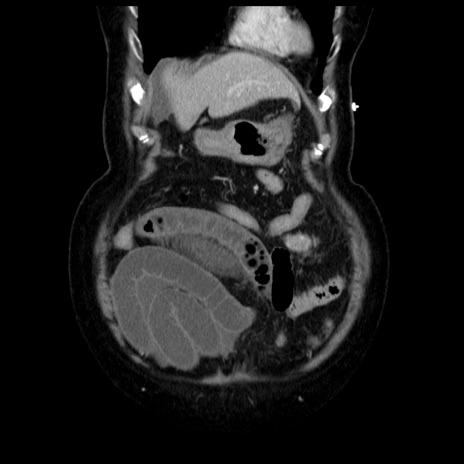

横断像

【症例】70歳代女性

【主訴】腹痛、嘔吐

【現病歴】15時間程前(昨晩)より腹痛あり。今朝になっても症状の改善なく、嘔吐あり。腹痛も増悪あり、救急外来受診。

【既往歴】子宮癌全摘術後

【身体所見】意識清明、BP 121/72mmHg、P 74bpm、SpO2 100%(RA)、腹部:平坦・軟、腸雑音ほぼ聴取せず。下腹部・心窩部・臍左上に圧痛あり。反跳痛なし。

【データ】WBC 10600、CRP 0.15